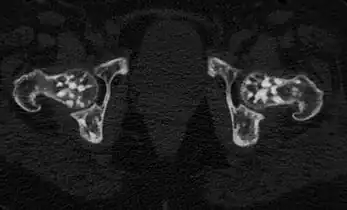

Osteopoikilosis of the hips on CT.